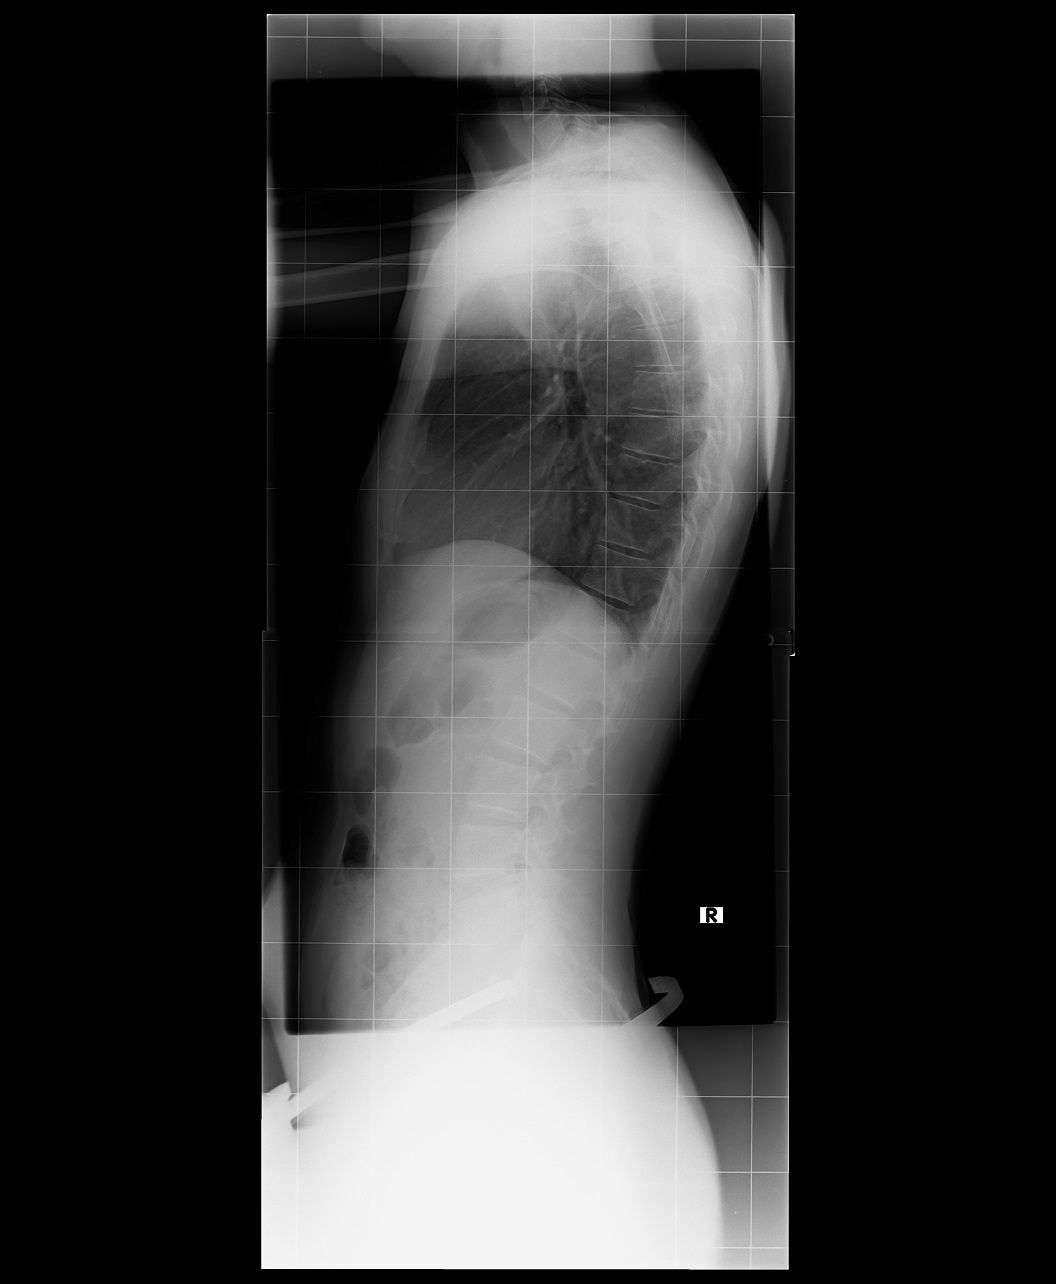

So ich hänge mal das Bild

meiner Wirbelsäule an.

Gruß Thomas

Ergebnis vorher 59 Grad mit Korsett 36 Grad.